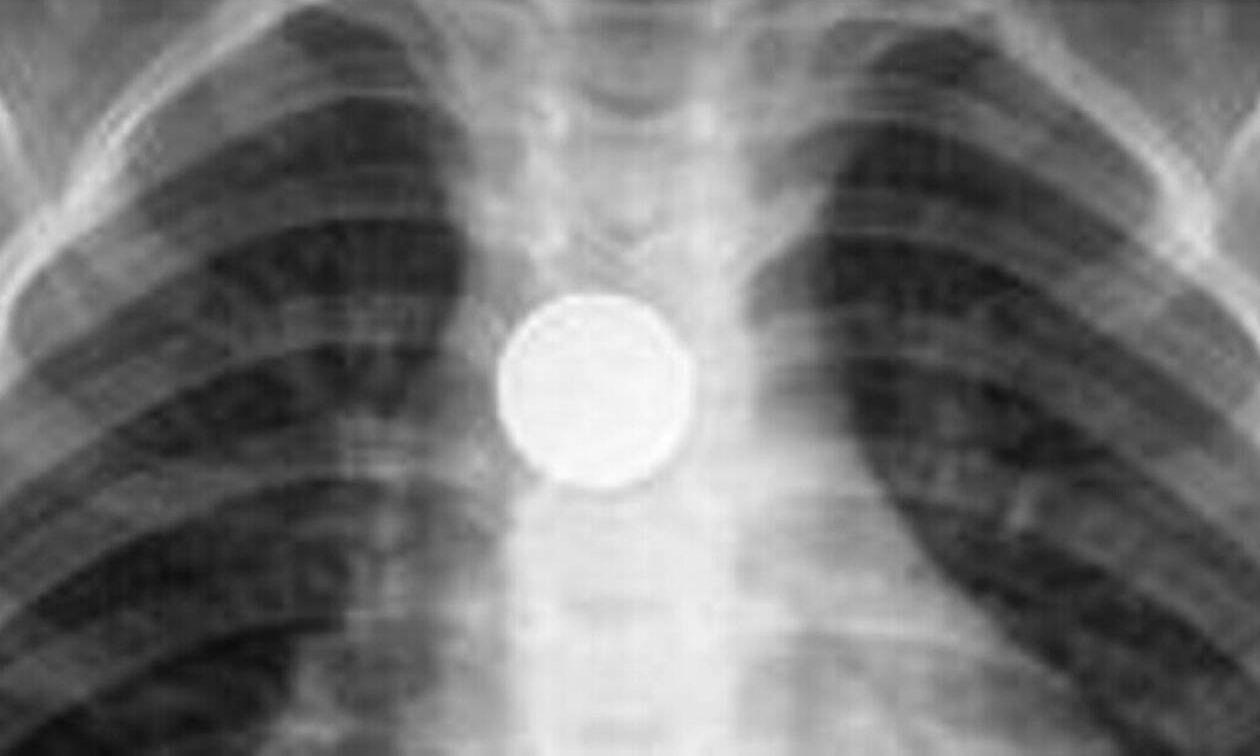

Τέλος καλό για το τρίχρονο που κατάπιε ξυραφάκι - Από καπάκια μέχρι παραμάνες «δοκιμάζουν» τα παιδιά

Η ηλικιακή ομάδα από έξι μηνών έως 4 ετών η πιο κρίσιμη για κατάποση επικίνδυνων αντικειμένων Περισσότερα...